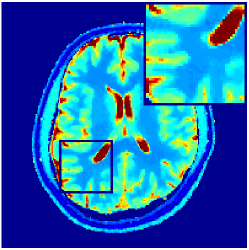

VI-F MRFResnet’s consistency with DM

Further to section VI-C validations, we compare parametric maps computed by DM and MRFResnet for the in-vitro and in-vivo scans, where the LRTV algorithm was applied for TSMI reconstruction. Results are summarised in Table III and for the in-vivo 2D spiral scan is illustrated in Figure 9. We observe very small differences in parametric maps (Table III) and particularly for the regions corresponding to white and grey matters predictions are highly consistent with each other (Figure 9).

| NRMSE (%) | T1 | T2 | PD |

|---|---|---|---|

| 2D/3D phantom scans | 0.08 / 0.13 | 0.12 / 0.13 | 0.78 / 1.43 |

| 2D/3D volunteer scans | 3.25 / 1.28 | 7.15 / 2.68 | 4.34 / 6.04 |

. diff T1(s) diff T2 (s) diff PD (a.u.)